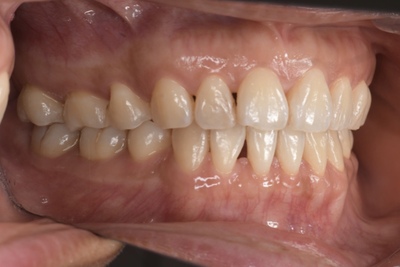

CASE 2

Before

After

基本情報

| 年齢・性別 | 30代・男性 |

| 主訴 | 歯石を取りたい |

| 治療内容 | 超音波スケーラーでの歯石除去 |

| 治療期間 | 60分 |

| 治療費 | 初診料を含め約4,500円 |

| リスク・副作用 | 歯ぐきに違和感や痛みを覚える場合がある。 1週間程度、歯を磨くといつもより出血することがある。 腫れていた歯ぐきが引き締まることで歯ぐきが下がった様に見える。 歯ぐきが下がることで歯がみしやすくなることがある。 一時的に歯の動揺(ゆれ)が増す場合がある。 |